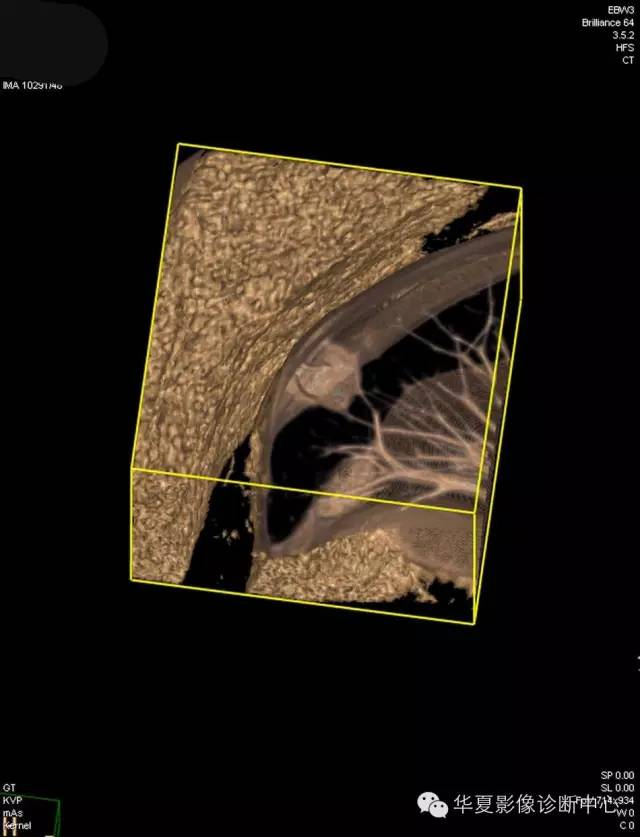

【病例学习】典型周围型肺癌CT病例一例

女,56岁,其父因肺癌去世,自觉胸部疼痛不适来诊要求拍胸片。

1.右肺上叶:肺组织1块,大小13×4×7cm。切面棕红色。2.右肺上叶肿物:灰白色组织一块,大小3×1×1.5cm。切面灰白色。3.右肺中叶结节:灰白色绿豆大组织1块。4.淋巴结:灰黑色绿豆大组织1块。

(右)肺中分化鳞状细胞癌。浸及胸膜。支气管残端切净。淋巴结未见癌转移(0/10)。